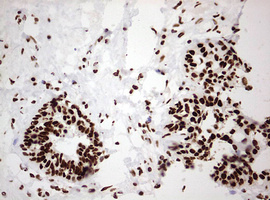

Immunohistochemical staining of paraffin-embedded Carcinoma of Human liver tissue using anti-HNRNPM mouse monoclonal antibody. (Heat-induced epitope retrieval by 10mM citric buffer, pH6.0, 120°C for 3min, M06017-2)